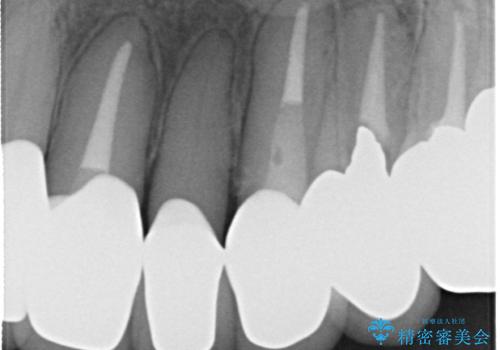

- 歯周外科・再根管治療後、クラウンを製作する。

・虫歯がとりきれていない

・接触部分がガタガタで適合の悪い金属

・全く無菌の努力がされていない根管治療

など、いい加減な治療は「治療」ではなく、むしろ医原性に歯の寿命を短くします。

最もよくないのは、クオリティの低い治療を何度も繰り返すことです。

時間をかけ、妥協なく治療を行い、今後の再治療の可能性を極力少なくするために、

費用や時間といった労力がかかってしまうのは当然のことです。